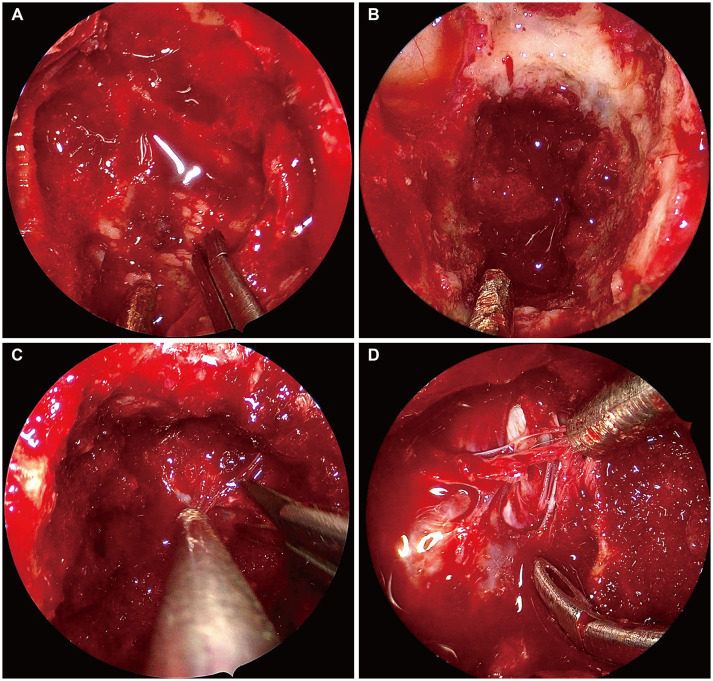

Giant cell tumors (GCTs) are locally aggressive primary bone tumors of osteoclast-like cells. Most GCTs occur within the long bones, and primary GCTs involving the clivus are extremely rare. We present the case of an 18-year-old boy with binocular horizontal diplopia with an insidious onset who was found to have a hypointense enhancing mass involving the clivus and left side dorsum sellae on magnetic resonance images. The tumor was completely resected via an endoscopic endonasal transclival approach, and histopathologic examination via immunohistochemistry indicated a GCT. The patient's left abducens nerve palsy improved slightly after surgery. Because of the rarity of GCTs, there is no consensus about the definitive treatment protocol. However, we suggest that gross total resection is the treatment of choice, and denosumab plays a critical role in patients with subtotal resection.